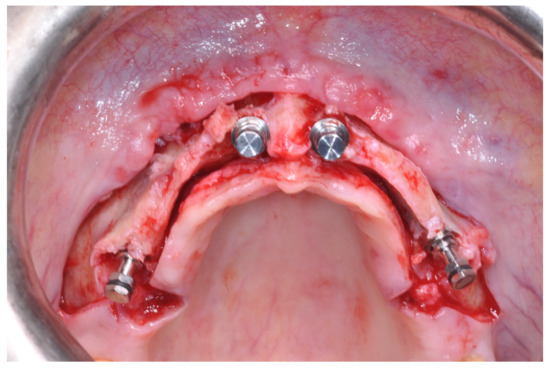

Patients rinsed with a chlorhexidine mouthwash (0.2%) for 1 min immediately prior to the intervention. Local anesthesia were administered using mepivacaine with adrenaline at ratios of 1:100,000 or 1:50,000. Crestal incisions were made with releasing incisions far away from the future membrane positioning and full thickness flaps were elevated. After the meticulous removal of all residual soft tissues in the regenerating site, copious bleeding was induced using a bone scraper (Safescraper Curve TWIST, META, Reggio Emilia, Italy) (Figure 1). A prosthetically guided implant placement was performed following the instructions of manufacturer (Thommen Medical, Grenchen, Switzerland). Only 1 patient had implants placed 9 months after bone augmentation because the initial bone thickness did not permit the primary stabilization of the implant fixtures (Figure 2, Figure 3, Figure 4, Figure 5, Figure 6, Figure 7 and Figure 8).

Figure 6. Surgical exposure of the augmented area 9 months after GBR.

Figure 7. Placement of the dental implants.

At this point, a non-resorbable high-density PTFE barrier (Cytoplast TXT-200, Osteogenics Biomedical, Lubbock, TX, USA) was designed on the basis of the bone defect shape and was distally blocked on the bone by two titanium pins (Kalos, Nike, Orbetello, Italy). A mixture of 50% autogenous bone harvested from the mandibular ramus with the use of a scraper and 50% inorganic bovine bone (Bio-Oss, Geistlich, Wolhusen, Switzerland) was placed in the recipient site and the membrane was pulled and blocked on the bone with two mesial pins. With this particular, and innovative, non-resorbable membrane management, the graft was compressed and fixed on the recipient bed (Figure 9, Figure 10 and Figure 11). The occlusal portion of the graft was then covered with a layer of a collagen resorbable barrier (Bio-Gide, Geistlich) (Figure 12) and peri-osteal incisions were performed to make the flap passive.

Figure 9. Occlusal view after implant placement.